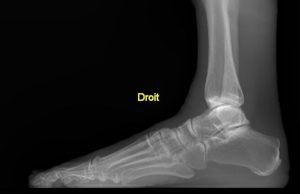

Il s’agit d’un appareil type cone beam permettant d’étudier en position débout, comme un scanner, les pieds, les chevilles et les genoux avec une très faible irradiation du patient comparé à un scanner conventionnel.

Il se destine aux pathologies liées aux troubles posturaux, aux douleurs des avants et arrières pieds.

Sa finesse d’image lui permet aussi d’être au cœur des bilans traumatiques et rhumatismaux de la cheville et du coup de pied.